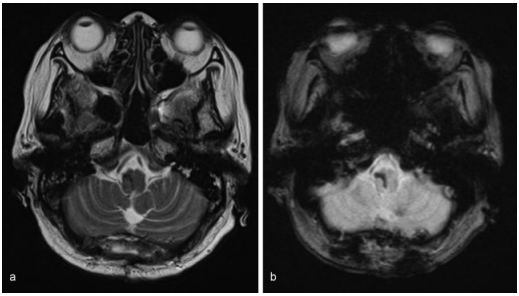

术前MR:脑干中脑巨大占位并发出血

手术结果:半坐位,正中小脑上入路,肿瘤全切历时约2小时,手术顺利